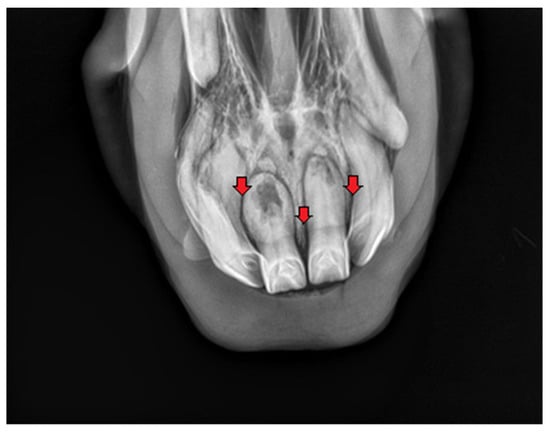

2.1.2. Case 2